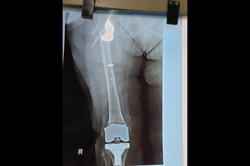

Mallet Finger